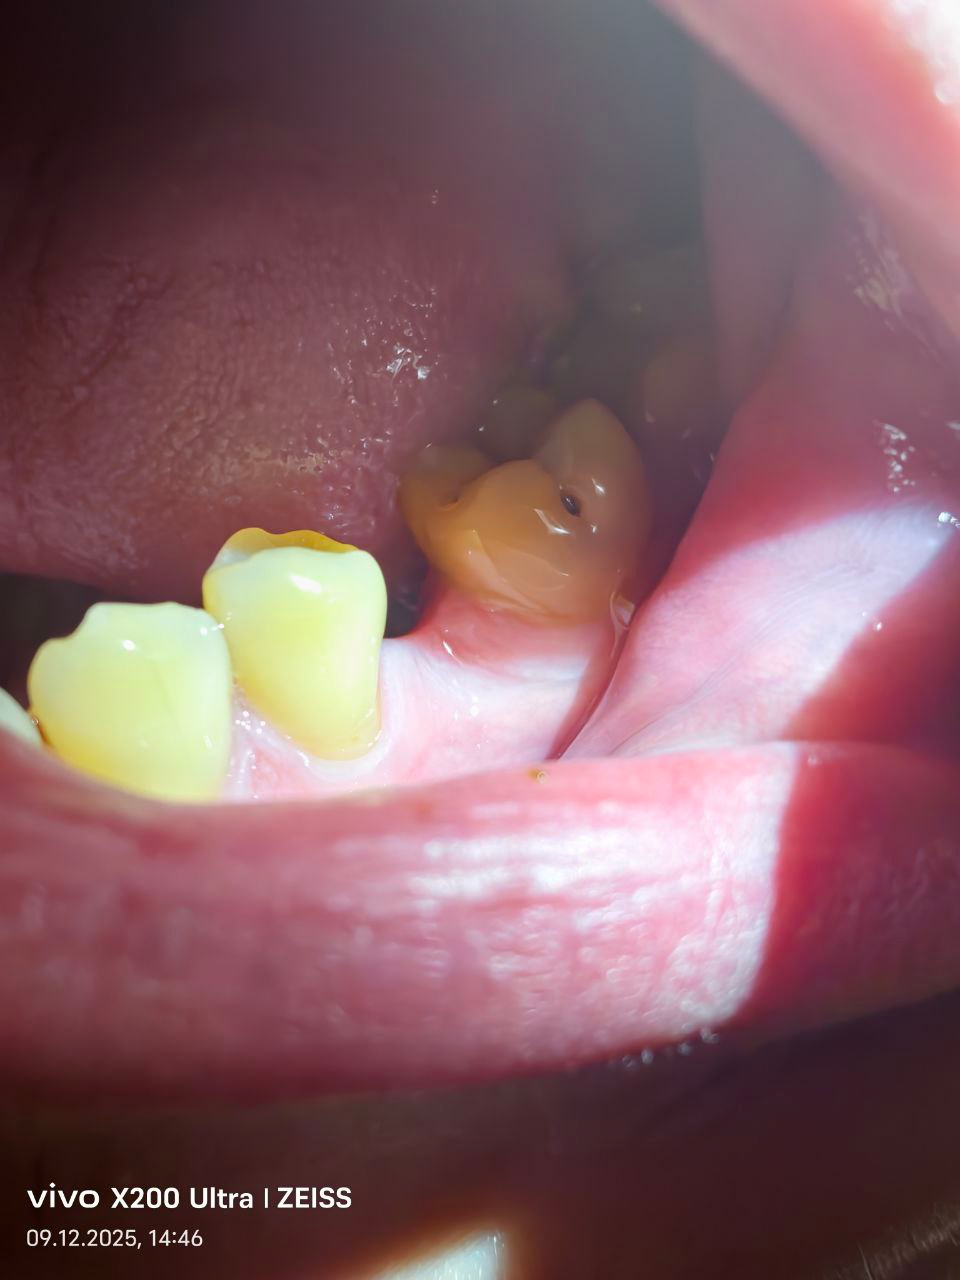

С какой вероятностью удалят этот черный зуб? Или есть смысл что-то с ним делать? Немного побаливает

С какой вероятностью удалят этот черный зуб? Или есть смысл что-то с ним делать?

Немного побаливает

Спрашиваю да бы сразу записываться по ОМС на удаление.

13 лет назад на нем была поставлена пломба, 11 лет назад она выпала, и вот как он выглядит сейчас